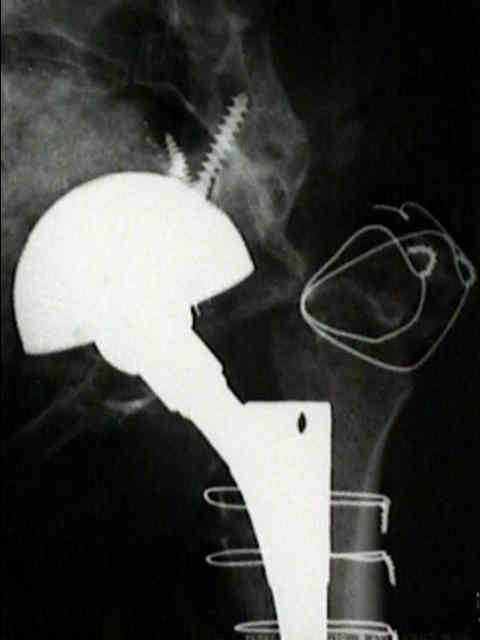

Loosening of Cemented Acetablar Components

(cemented acetabular component)

- radiolucency upto 2 mm wide with or without a surrounding fine line of density may develop in one or more of the the three zones about cement mass in the pelvis;

- as in the femur, radiolucency is produced by the dense fibrous membrane and in some areas, fibrocartilage that forms about the surface of the cement and the surrounding shell of reactive bone;

- loosening commonly occurs at the stem cement interface, but it rarely occurs at the cup cement interface;

definite loosening

- migration of component of more than 5 mm;

- crack in cement mantle;

probable loosening

- continuous radiolucent line > 1-2 mm wide at the bone cement interface;

- as pointed out by Hodgkins et al 1988, the finding of a continuous radiolucent line about the acetabular component indicates loosening in 94% of patients;

possible loosening

- non circumferential radiolucency which extends at least 50% around the bone cement interface;